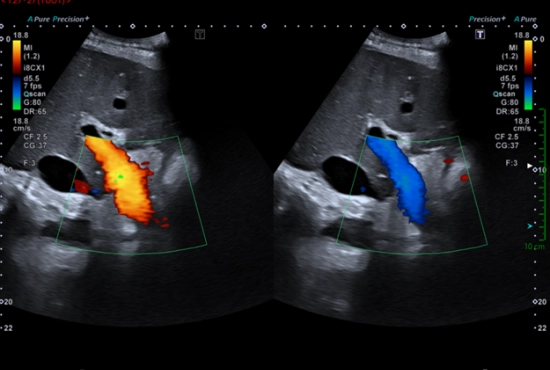

"Mais dites donc la SFEcho quelle est la différence entre le mode Doppler Couleur et le Doppler Énergie ?"